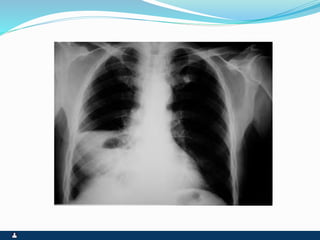

DERRAME PLEURAL

SINTOMAS SINAIS

 DEPENDENTES DA

ETIOLOGIA

 DOR PLEURÍTICA

 TOSSE SECA

 DISPÉIA

 TAQUIPNÉIA

 ABAULAMENTO HOMOLATRAL

DO TÓRAX E ESPAÇOS

INTERCOSTAIS

 DESVIO CONTRALATERAL DO

MEDIASTINO

 EXPANSIBILIDADE REDUZIDA

 FTV ABOLIDO

 MACICEZ

 MV ABOLIDO

 ESTERTORES BRÔNQUICOS E

ALVEOLARES NAS ÁREAS DE

TRANSIÇÃO

 COLUNA MACIÇA EM T11 – SINAL

DE SIGNORELLI

DERRAME PLEURAL LOCULADO